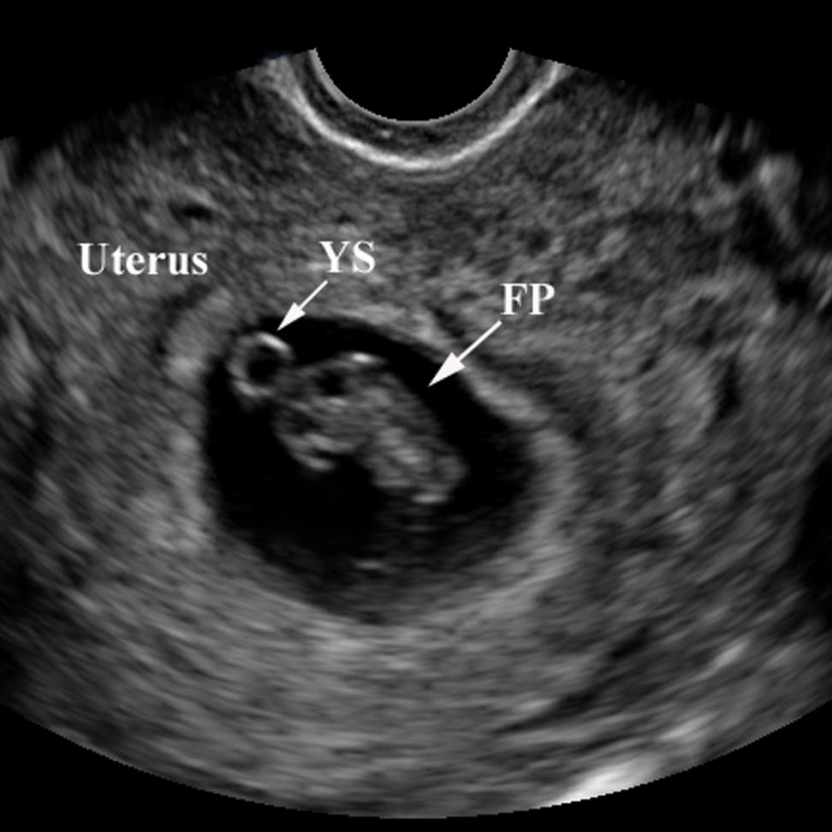

ultrasound at 3 weeks pregnant pictures

Understanding Your Baby’s Development in Week 3

3 Weeks Pregnant – Pregnancy Week-by-Week

Yolk sac | Image | Radiopaedia.org